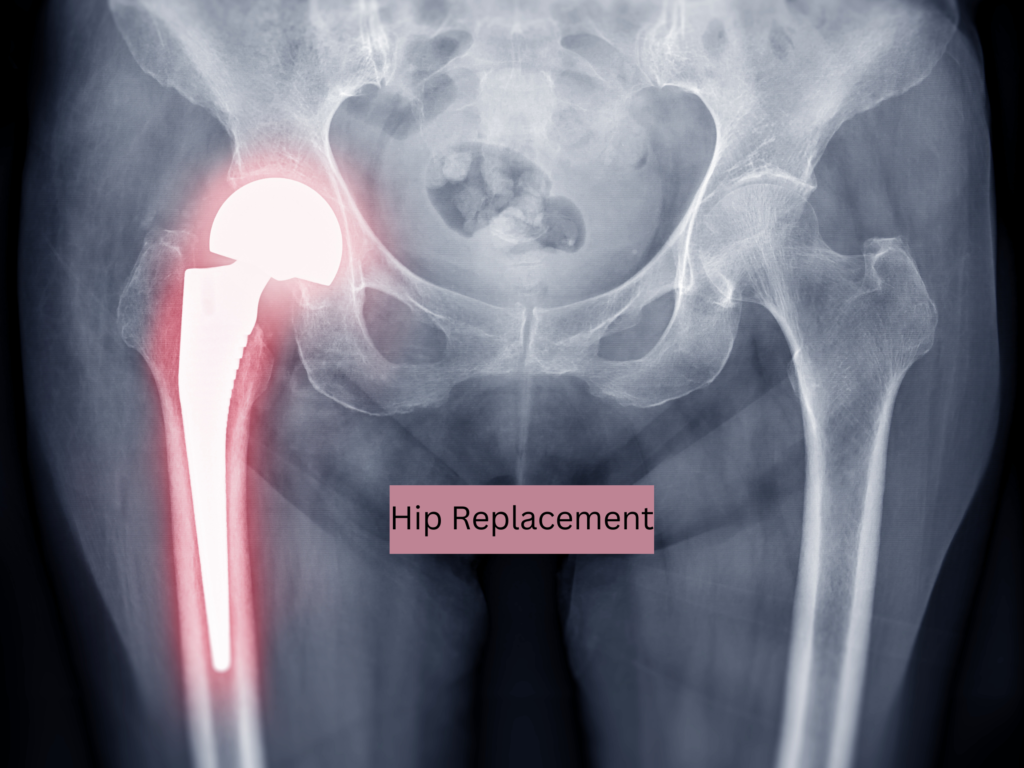

Hip Replacement

What is a hip replacement?

According to the Mayo Clinic, a hip replacement is surgery to remove damaged sections of the hip joint and replace them with artificial parts.

In simple terms: part of your femur and hip joint is removed and replaced with a prosthetic joint.

Hip replacements are typically performed when the joint is severely damaged—most commonly from arthritis.

Other causes can include hip dysplasia, osteonecrosis, or rheumatoid arthritis.